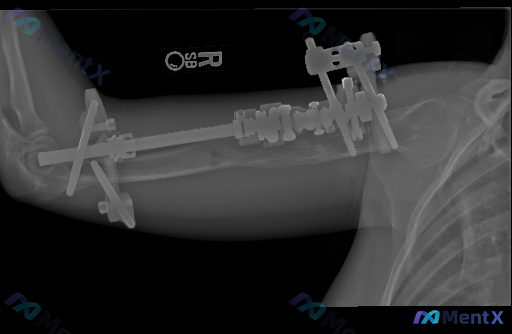

整理到一张右侧肱骨的正位X光片,先给大家同步一下客观的影像表现:

- 骨骼结构:右侧肱骨干中段皮质连续性中断,存在明显的大段骨质缺损;缺损边缘有不同程度的硬化或退缩,目前看不到明确的骨痂连接。

- 固定装置:可见外固定架,近端钢针穿过肱骨近端,远端钢针固定于肱骨髁上区域,中间有长杆连接,维持了肱骨长度和大致对线。

- 关节情况:肩关节、肘关节的位置关系基本对合,关节间隙尚可,没有看到明显脱位。

- 其他:肱骨残端骨质密度不太均匀,针道周围软组织密度稍高,但没有明显的广泛肿胀或异常气体影;骨骺线已闭合,是成人骨骼。